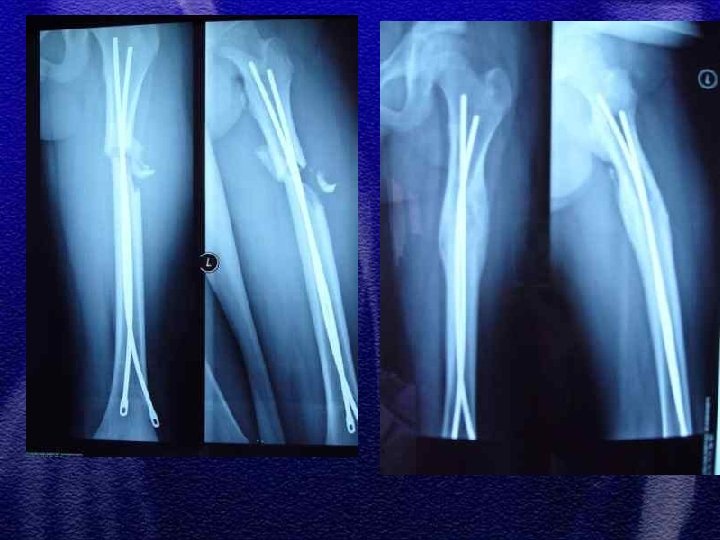

§ Do 4 roku życia leczenie wyłącznie zachowawczewyciąg plastrowy lub szkieletowy w zależności od wieku § Większość złamań do 10 r. ż. - wyciąg szkieletowy ok. 3 tyg. , a następnie gips biodrowy od 3 do 6 tygodni w zależności od wieku § Leczenie operacyjne rozważa się po 10 roku życia a metody zespolenia to: Zespol, pręty Endera, Rusha, stabilizatory zewnętrzne